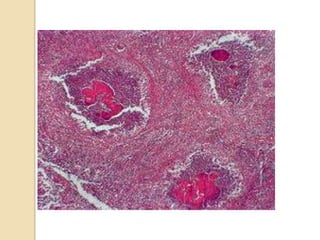

BIOPSY under guide CT

Slowly growing

gram +ve

bacteria

: actinomyces

israeli

LIVER BIOPSY

Adefinitive diagnosis is histopathology tests on

sample obtained under screen

BIOPSY under guideCT Slowly growing gram +ve bacteria : actinomyces israeli